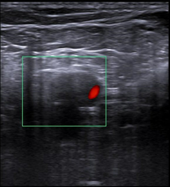

En ecografía clínica realizada por dolor de rodilla derecha se aprecia en región posterior vena poplítea que no comprime. En modo Doppler: defecto de repleccion del vaso por probable trombo intraluminal.

Doppler miembro inferior derecho: Ocupación de vena poplítea por material ecogénico, no permeable ni compresible, sin flujo doppler presente. Venas femoral común, superficial y troncos infrapoplíteos permeables y compresibles. Safena mayor y ambos cayados permeables y compresibles. Conclusión: TVP vena poplítea derecha.